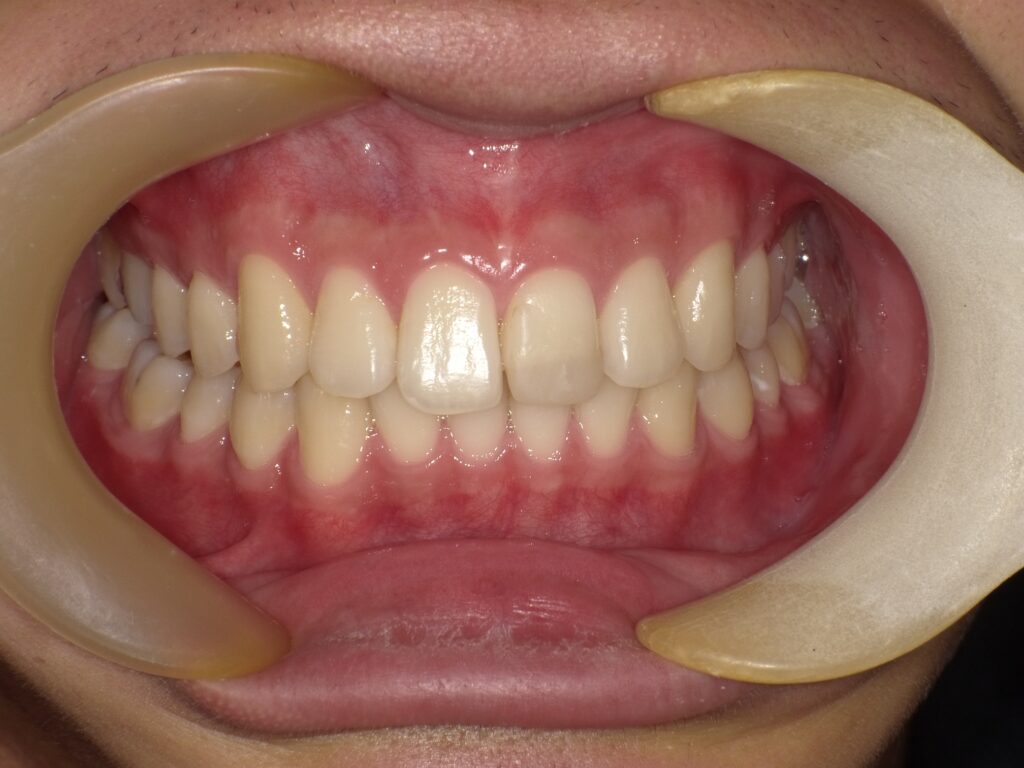

治療後